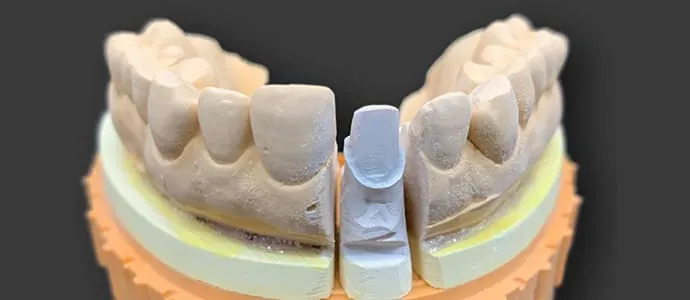

ダイレクトボンディングで、すきっ歯が1日で改善できます

治療前

治療後

ダイレクトボンディングは、お口の中で直接コンポジットレジンを盛り付け、形を整えていく治療法です。

治療は基本的に1回で完了し、歯をほとんど、またはまったく削ることなく行えるため、身体への負担が少ないのが特長です。多くの場合、麻酔を使用せずに治療が可能で、短時間で自然な見た目に仕上げることができます。